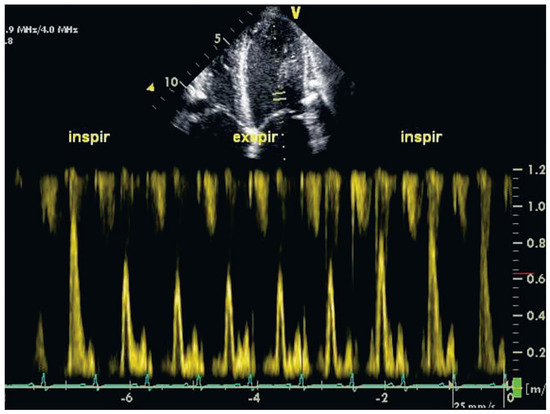

A 56-year-old man was admitted with massive signs of right heart failure, which had evolved over weeks. Chest X-ray revealed extensive pericardial calcifications in the lateral view ( Figure 1). Transthoracic echocardiography showed only mildly impaired biventricular systolic function but a dilated inferior vena cava without respiratory variability. The peak early mitral annular velocities (e’) assessed by pulsed wave tissue Doppler at the septal and lateral mitral annulus were 8 and 6 cm/s, and the ratio of the peak early transmitral velocity (E) to e’ (E/e’), based on an average e’ of 7 cm/s, was only 10 (Figure 2A,B,D). The pulmonary venous flow was clearly abnormal however (Figure 2C). There was an exaggerated respiratory variability of mitral in-flow (Figure 3).

Figure 3. Transthoracic Doppler echocardiography demonstrating the exaggerated respiratory variability of mitral inflow. Mitral inflow is reduced during inspiration, but increases during expiration.